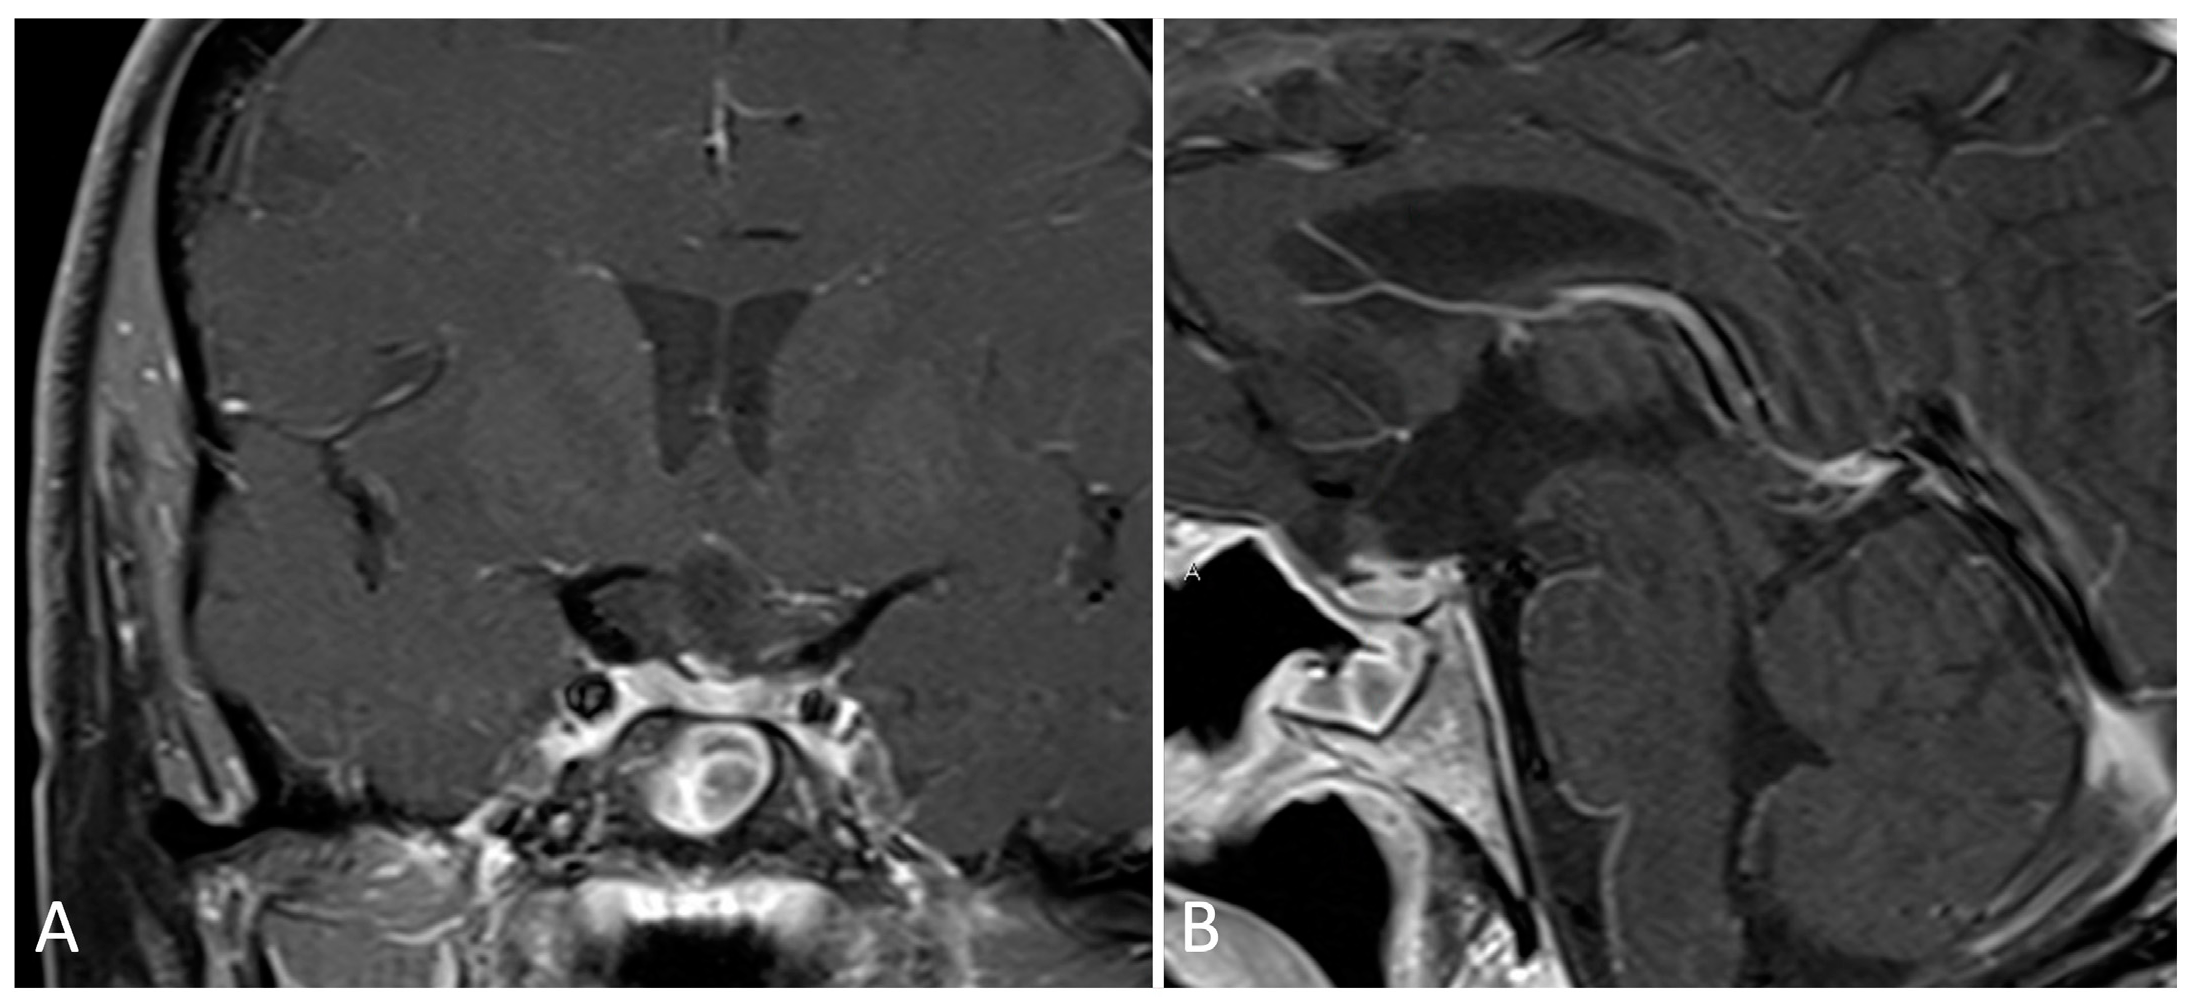

3.4.2. Illustrative Case

- Sacrifice of the sphenopalatine artery in the transpterygoid approach precludes an ipsilateral nasoseptal flap.

- Skeletonization of the maxillary nerve leads to the ‘quadrangular space’ and Meckel’s cave.

- Skeletonization of the vidian nerve leads to the lacerum segment of the ICA.

- The contralateral transmaxillary approach may be a useful back up option for lateral petrous pathologies approaching the IAC.